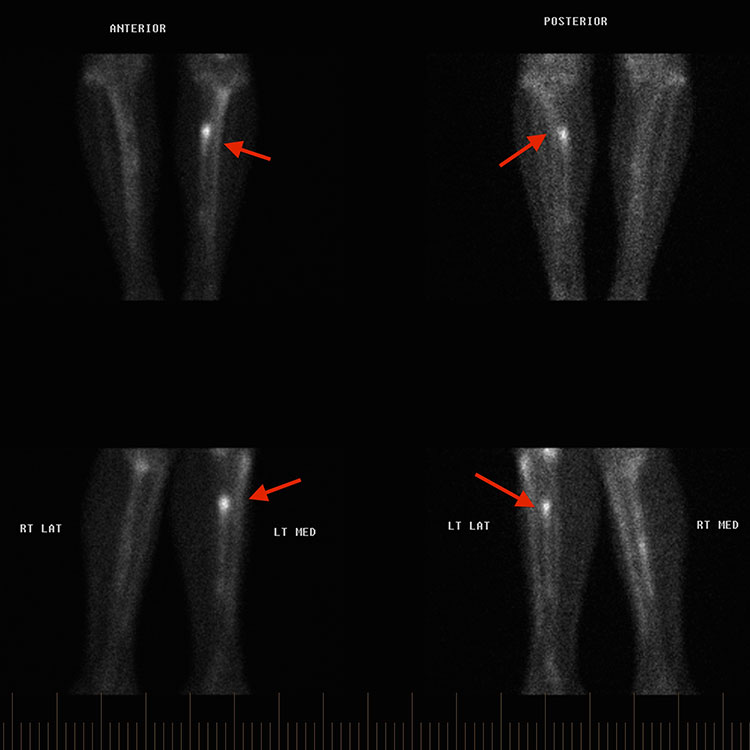

1. Accurate giagnosis 정확한 진단 : 피로반응이나 골절을 정확하게 진단하는 것이 효과적인 관리의 가장 중요한 요소.

주상골 (Navicular): 진단 및 치료가 특히 어렵습니다. 6~8주 동안 비체중 부하 깁스 고정이 치료의 선택이며, 진단이 지연된 경우에도 마찬가지입니다. 비유합, 지연 유합 또는 골절 부위의 심한 분리가 있는 경우 수술적 고정이 지시됩니다.

내측 복사뼈 (Medial malleolus): 본질적으로 불안정하고 비유합되기 쉬우므로 고위험 피로골절로 간주됩니다. X-ray나 CT에서 골절선이 보이지 않는 경우 4~6주 동안 적극적인 고정(엄격한 비체중 부하)이 필요합니다. 골절선이 명확한 경우 **개방 정복 및 내고정술(ORIF)**이 선택 치료입니다.